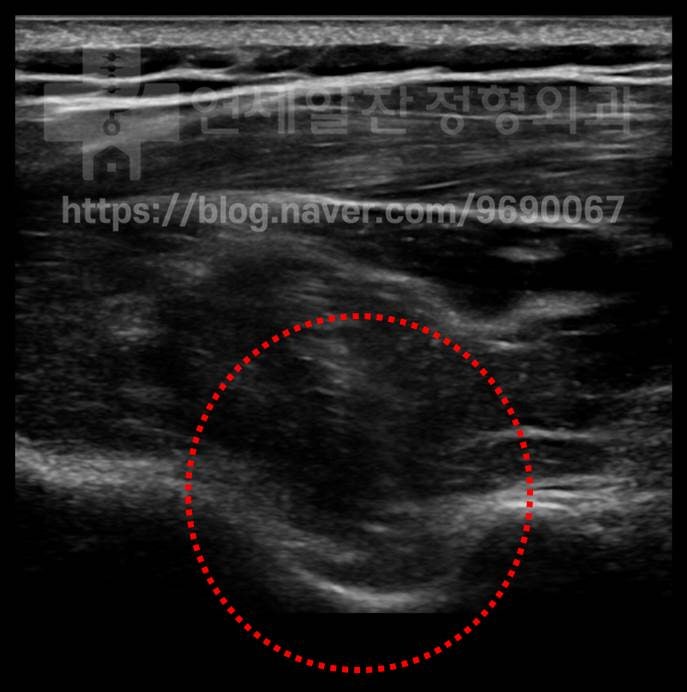

초음파상 노란색 원 안의 검은 부분이 물혹입니다.

초음파로 위치를 확인한 후 주사기를 이용하여 (파란색 선) 물혹을 제거하고 난 후 앞에 보였던 물혹이 완전히 제거된 것이 관찰됩니다.